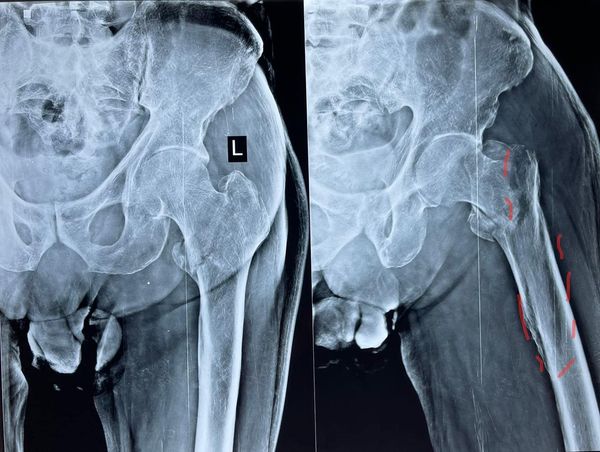

Intertrochanteric fractures of the femur that extend down into femoral shafts are sometimes tricky to handle, especially if the patient is 78 years old with multiple medical comorbidities. Such fractures should always be fixed however to give them a better chance in life, these long cephalomedullary nails (longfin) are best in such scenarios, these implants should also be used in most unstable intertrochanteric femur fractures in severe osteoporosis for a chance of better fixation.